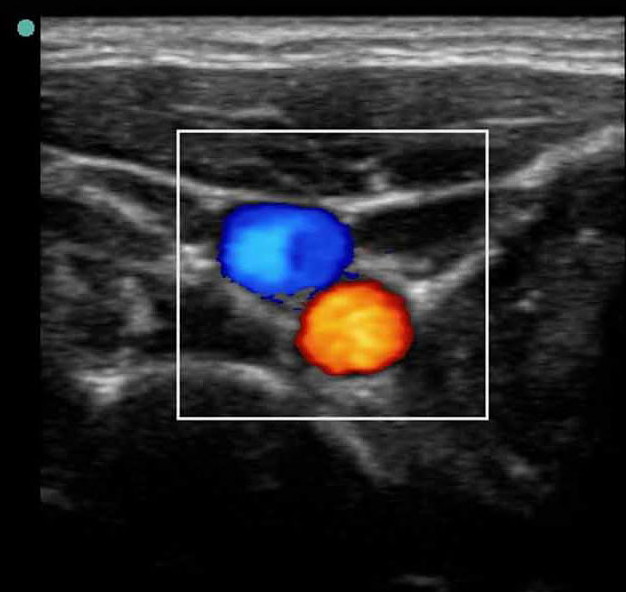

バスキュラーアクセス3カラー画像

S シリーズ:IJV 短軸3。